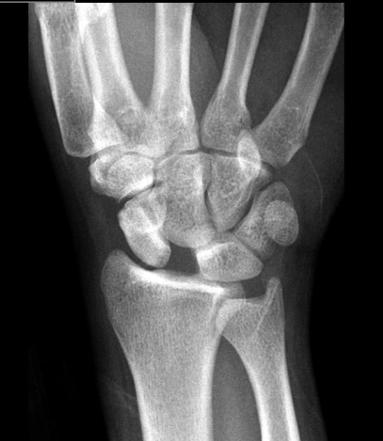

This carpal injury is named for two comedians that all you children are too young to remember?

Scapholunate dislocation

"David Letterman sign"

"Terry Thomas sign"